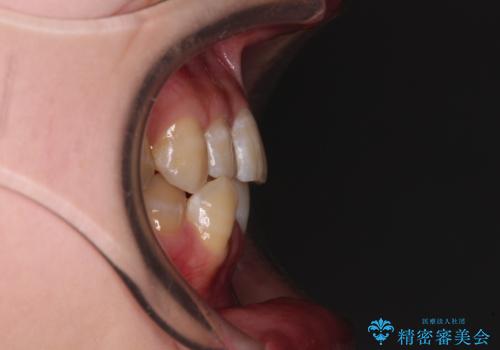

- 下顎の八重歯を気にして来院された患者様です。

下顎前歯にデコボコが集中していたため、顎間ゴムによる後方移動とIPR(歯と歯の間を削ること)により歯列を整えることとしました。

下顎前歯のデコボコが集中しており、奥歯の咬み合わせは、上顎に対して下顎が前方位にある状態でした。下顎の歯列を後方へ移動させる治療はインビザラインの得意とするところですので、1年程度で無事に治療を終えることができました。